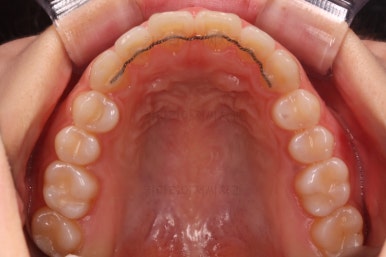

장치 부착 시점의 사진입니다.

장치를 붙이고 철사가 구불구불 들어가게 되면 그제서야 "이렇게 많이 틀어져 있었구나"를 더 잘 느 끼시게 됩니다.

이번에 사용한 장치는 엠파워 클리어라고 하는 자가결찰 세라믹 장치인데 같은 계열로는 엠파워 클리어를 비롯해 클리피씨 등이 있어요.

치아에 붙는 장치가 치아색과 비슷한 세라믹으로 만들어져 있고 철사를 붙잡아 주는 클립이 달려 있어 스스로 철사를 묶을 수 있다고 해서 "자가결차" 이라고 표현해요.

클리피씨 장치가 가장 유명하긴 하지만 매우 다양한 제품이 있고 거의 비슷한 장치이기 때문에 의사와 상의 하에 선택을 하시면 됩니다.

엠파워 장치는 미국, 클리피씨는 일본장치이며 기능적으로는 둘 다 우수한 장치입니다.